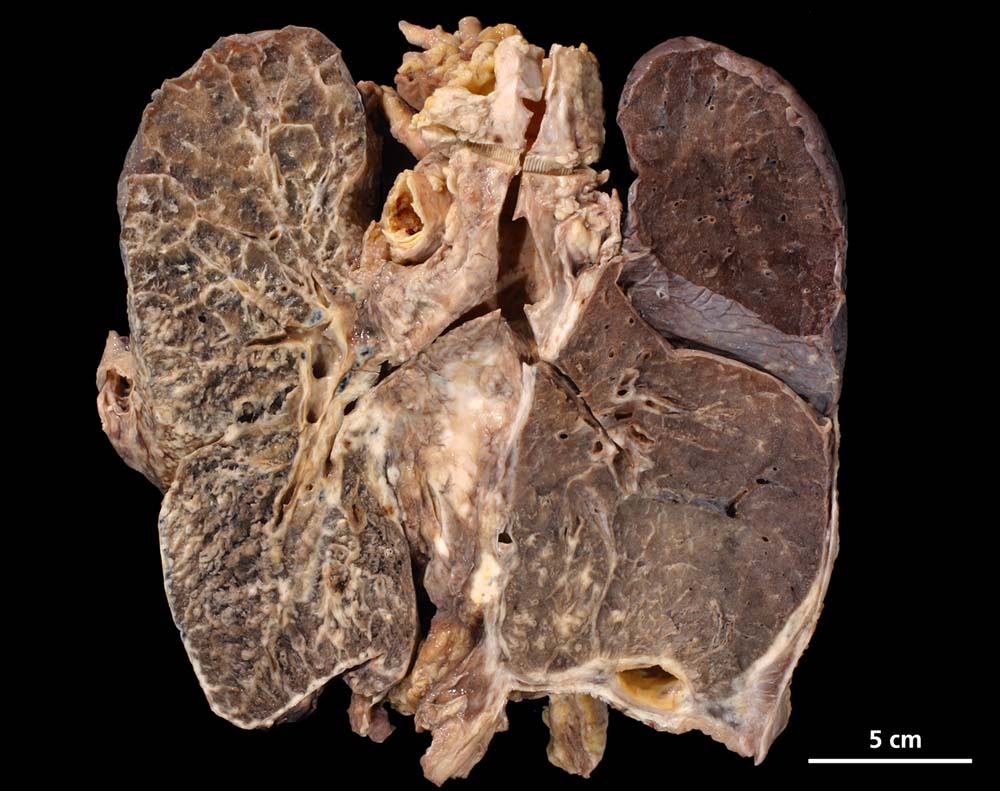

Das metastatische Wachstumsmuster von primären Bronchuskarzinomen und extrapulmonalen Tumoren innerhalb der Lunge ist variabel. Hämatogene Metastasen imponieren makroskopisch als multiple scharf begrenzte rundliche Knoten in allen Lappen meist in peripherer Lage. Der metastatische Befall von Lymphknoten kann durch direkte Tumorinfiltration durch den Primärtumor erfolgen (=per continuitatem) oder über die Lymphgefässe. Bei einer ausgeprägten lymphogenen Tumorausbreitung erscheinen subpleurale mit Tumor gefüllte Lymphgefässe makroskopisch als prominente weisse Streifen. Mikroskopisch lassen sich Tumorinfiltrate in peribronchialen und perivaskulären Lymphgefässen nachweisen (=Lymphangiosis carcinomatosa). Hepatozelluläre Karzinome metastasieren typischerweise in Form von Tumorembolien (> 1279) hämatogen in die Lunge.

Im Thoraxröntgenbild kann die Lymphangiosis carcinomatosa häufig nicht vom interstitiellen Lungenödem unterschieden werden. Die Ausbreitung der Tumorinfiltrate ist aber in der Regel nicht so symmetrisch und gleichmässig wie beim interstitiellen Lungenödem. Weitere Differentialdiagnosen: Sarkoidose, Silikose, exogen allergische Alveolitis, fibrosierende Alveolitis, Lymphom oder Kaposi Sarkom.